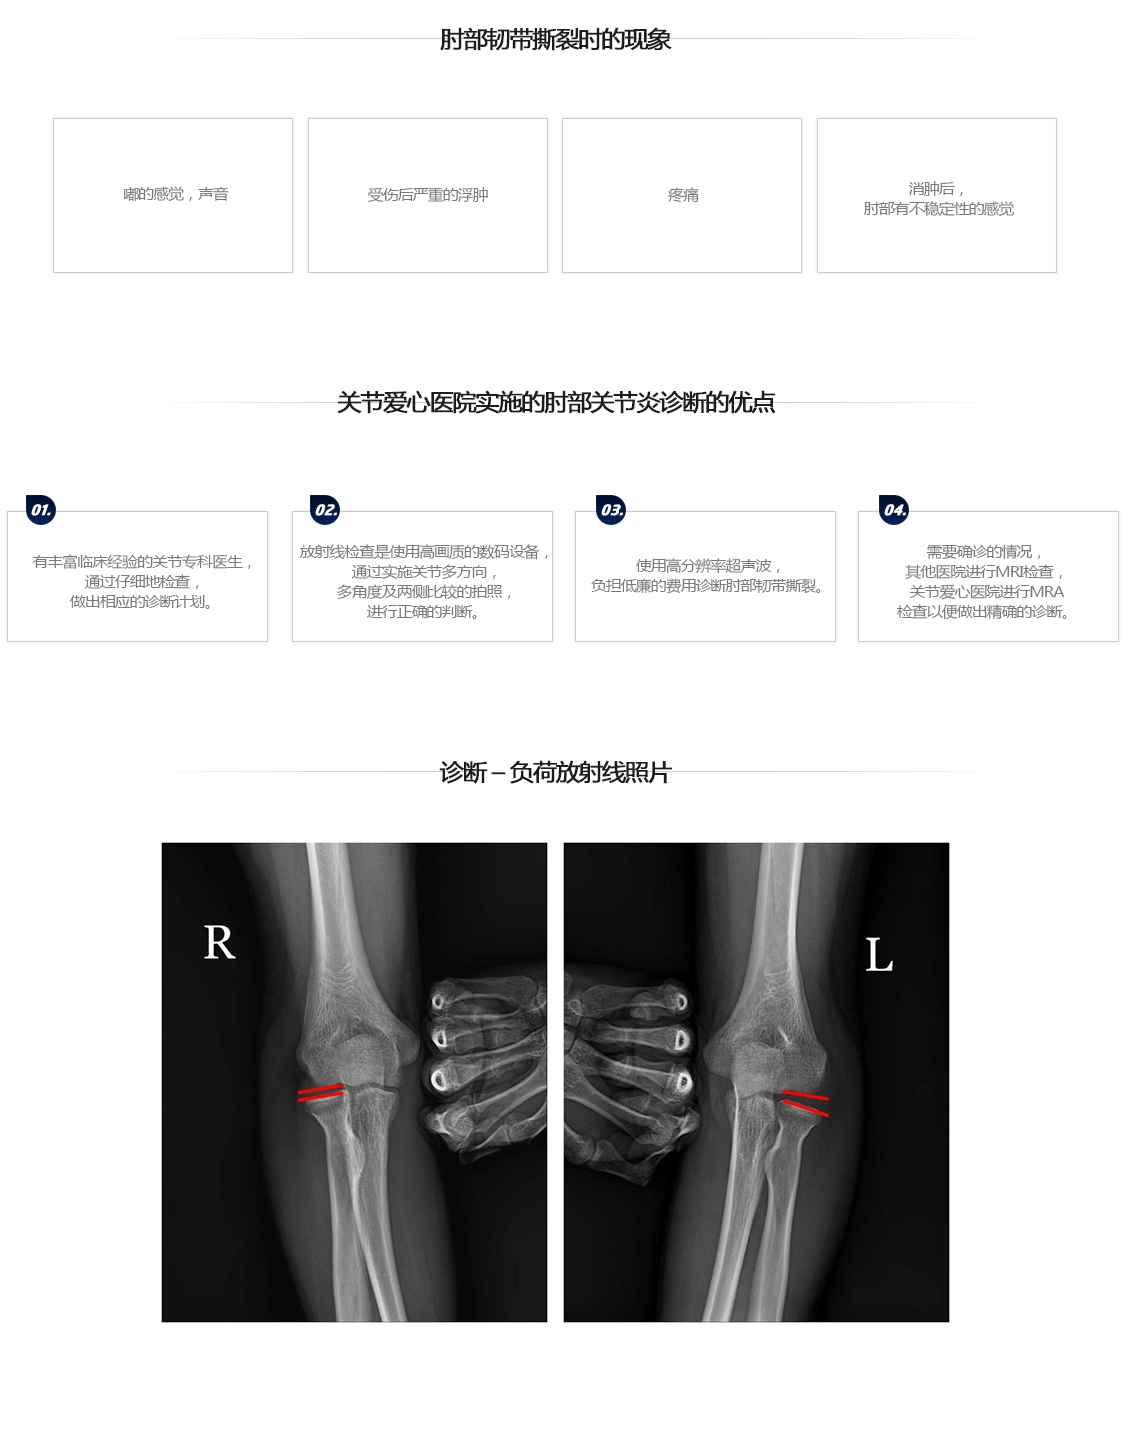

胳膊肘韧带撕裂